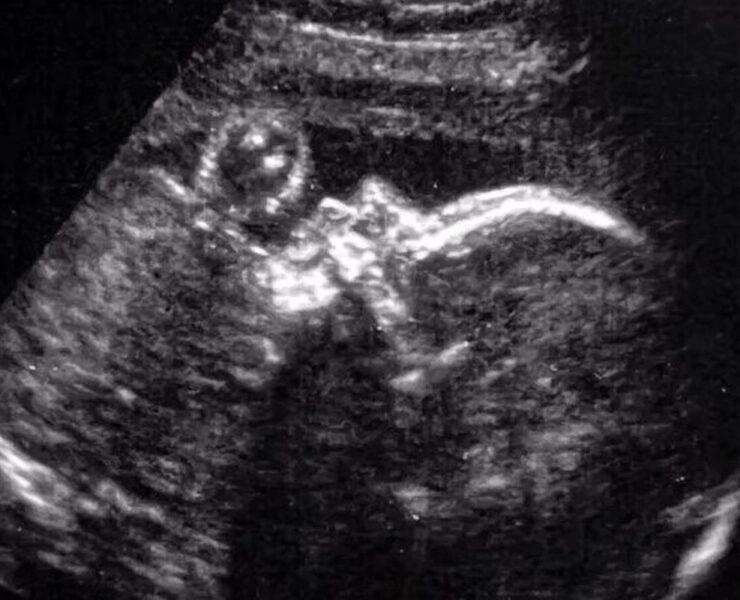

Και τα βοηθάει να ρυθμίζουν την αναπνοή τους